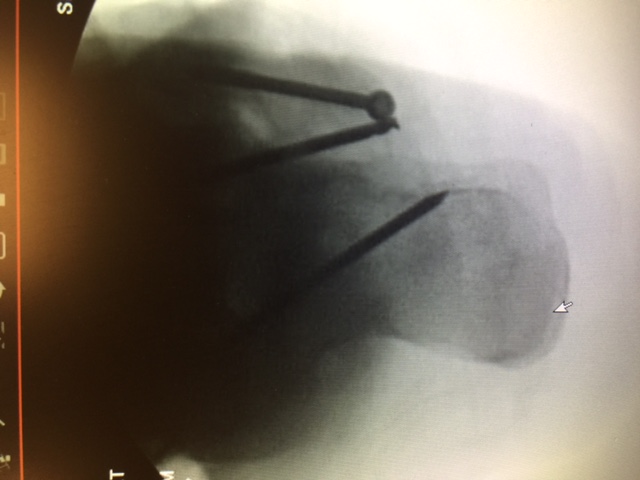

Additional emerging concepts with regard to beaming within our institution include the use of titanium trusses for cases involving significant midfoot bone loss. We have performed several of these reconstructions with good long-term limb salvage results. Structurally speaking, titanium trusses accept and resist the same loads as beams. A benefit of a truss is the bending stiffness and bending strength is a factor of 4 or above the structural mass required for the midfoot, which can easily resist failure.

In our experience, the mechanical forces of the midfoot in compression are enough to place the wedge without the need for fixation. However, we have routinely delivered beam screws through the titanium cage. We believe the truss acts as an additional load-bearing device with an independent section modulus that substitutes for the midfoot bone. When working in combination with a beam, we believe that the truss deflects forces from the beam.

Additionally, the titanium truss is filled with autogenous bone graft and orthobiologics, allowing for incorporation through the osteotomy site. This device allows for reconstruction in situations of excessive bone loss, acting as a replacement with the capacity for ingrowth. Follow-up demonstrates improved angular deformity correction with complete bridging on computed tomography (CT) scan.